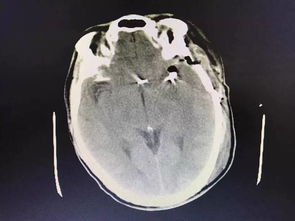

病情分析: 腦動(dòng)脈血管瘤夾閉手術(shù)后偏癱失語(yǔ) 病情指導: 需要繼續治療,應該是傷及神經(jīng)了,腦血管瘤的治療:全切除腫瘤可治愈此病,但由于腦血管瘤的位置,瘤體的大小往往使瘤體不能完全切除,術(shù)中瘤結節的遺漏亦是腫瘤復發(fā)的一個(gè)因素。

中醫治療:服用單方含量16%以上的人參皂苷Rh2(護命素),三七,蟲(chóng)草等具有抗腫瘤功效的藥物,特別是人參皂苷Rh2(護命素),是現代化中藥分子藥物,具有提高免疫力和抗腫瘤的雙重功效,是小分子結構,易透過(guò)人體血腦屏障,發(fā)揮功效,控制和抑制殘留腦部腫瘤細胞的生長(cháng)。